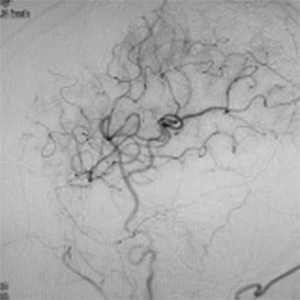

閉塞した脳血管

バイパス術で増加した脳血管

バイパス術により脳血流が正常化